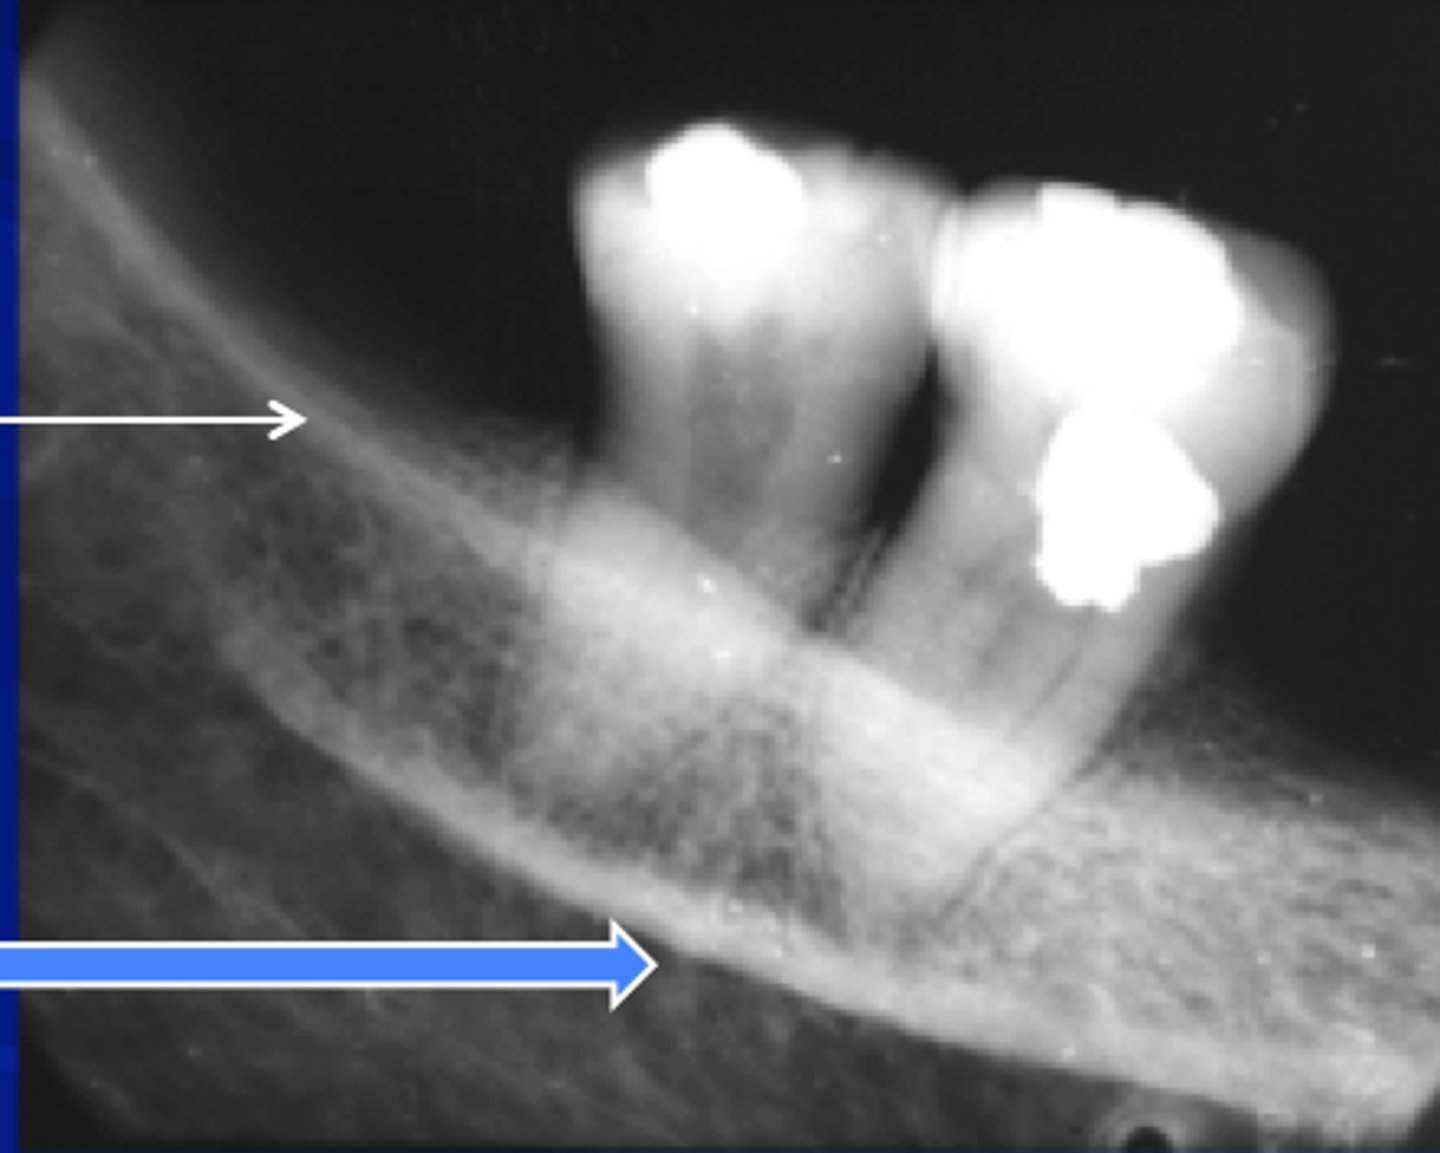

external oblique ridge

dense white line distal to the last molar and moving across root of molars

internal oblique ridge

located below the external oblique ridge

less dense

ridge of bone that extends across roots

mandibular canal

border on top and bottom by a white line

passageway for nerves and blood vessels